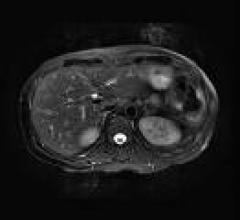

September 9, 2009 - The ACR has convened a LI-RADS (Liver Imaging Reporting and Data System) Committee to develop a system for standardized reporting and data collection for CT and MR imaging surveillance for hepatocellular carcinoma (HCC). The production of CT-MR LI-RADS aims to do the following: